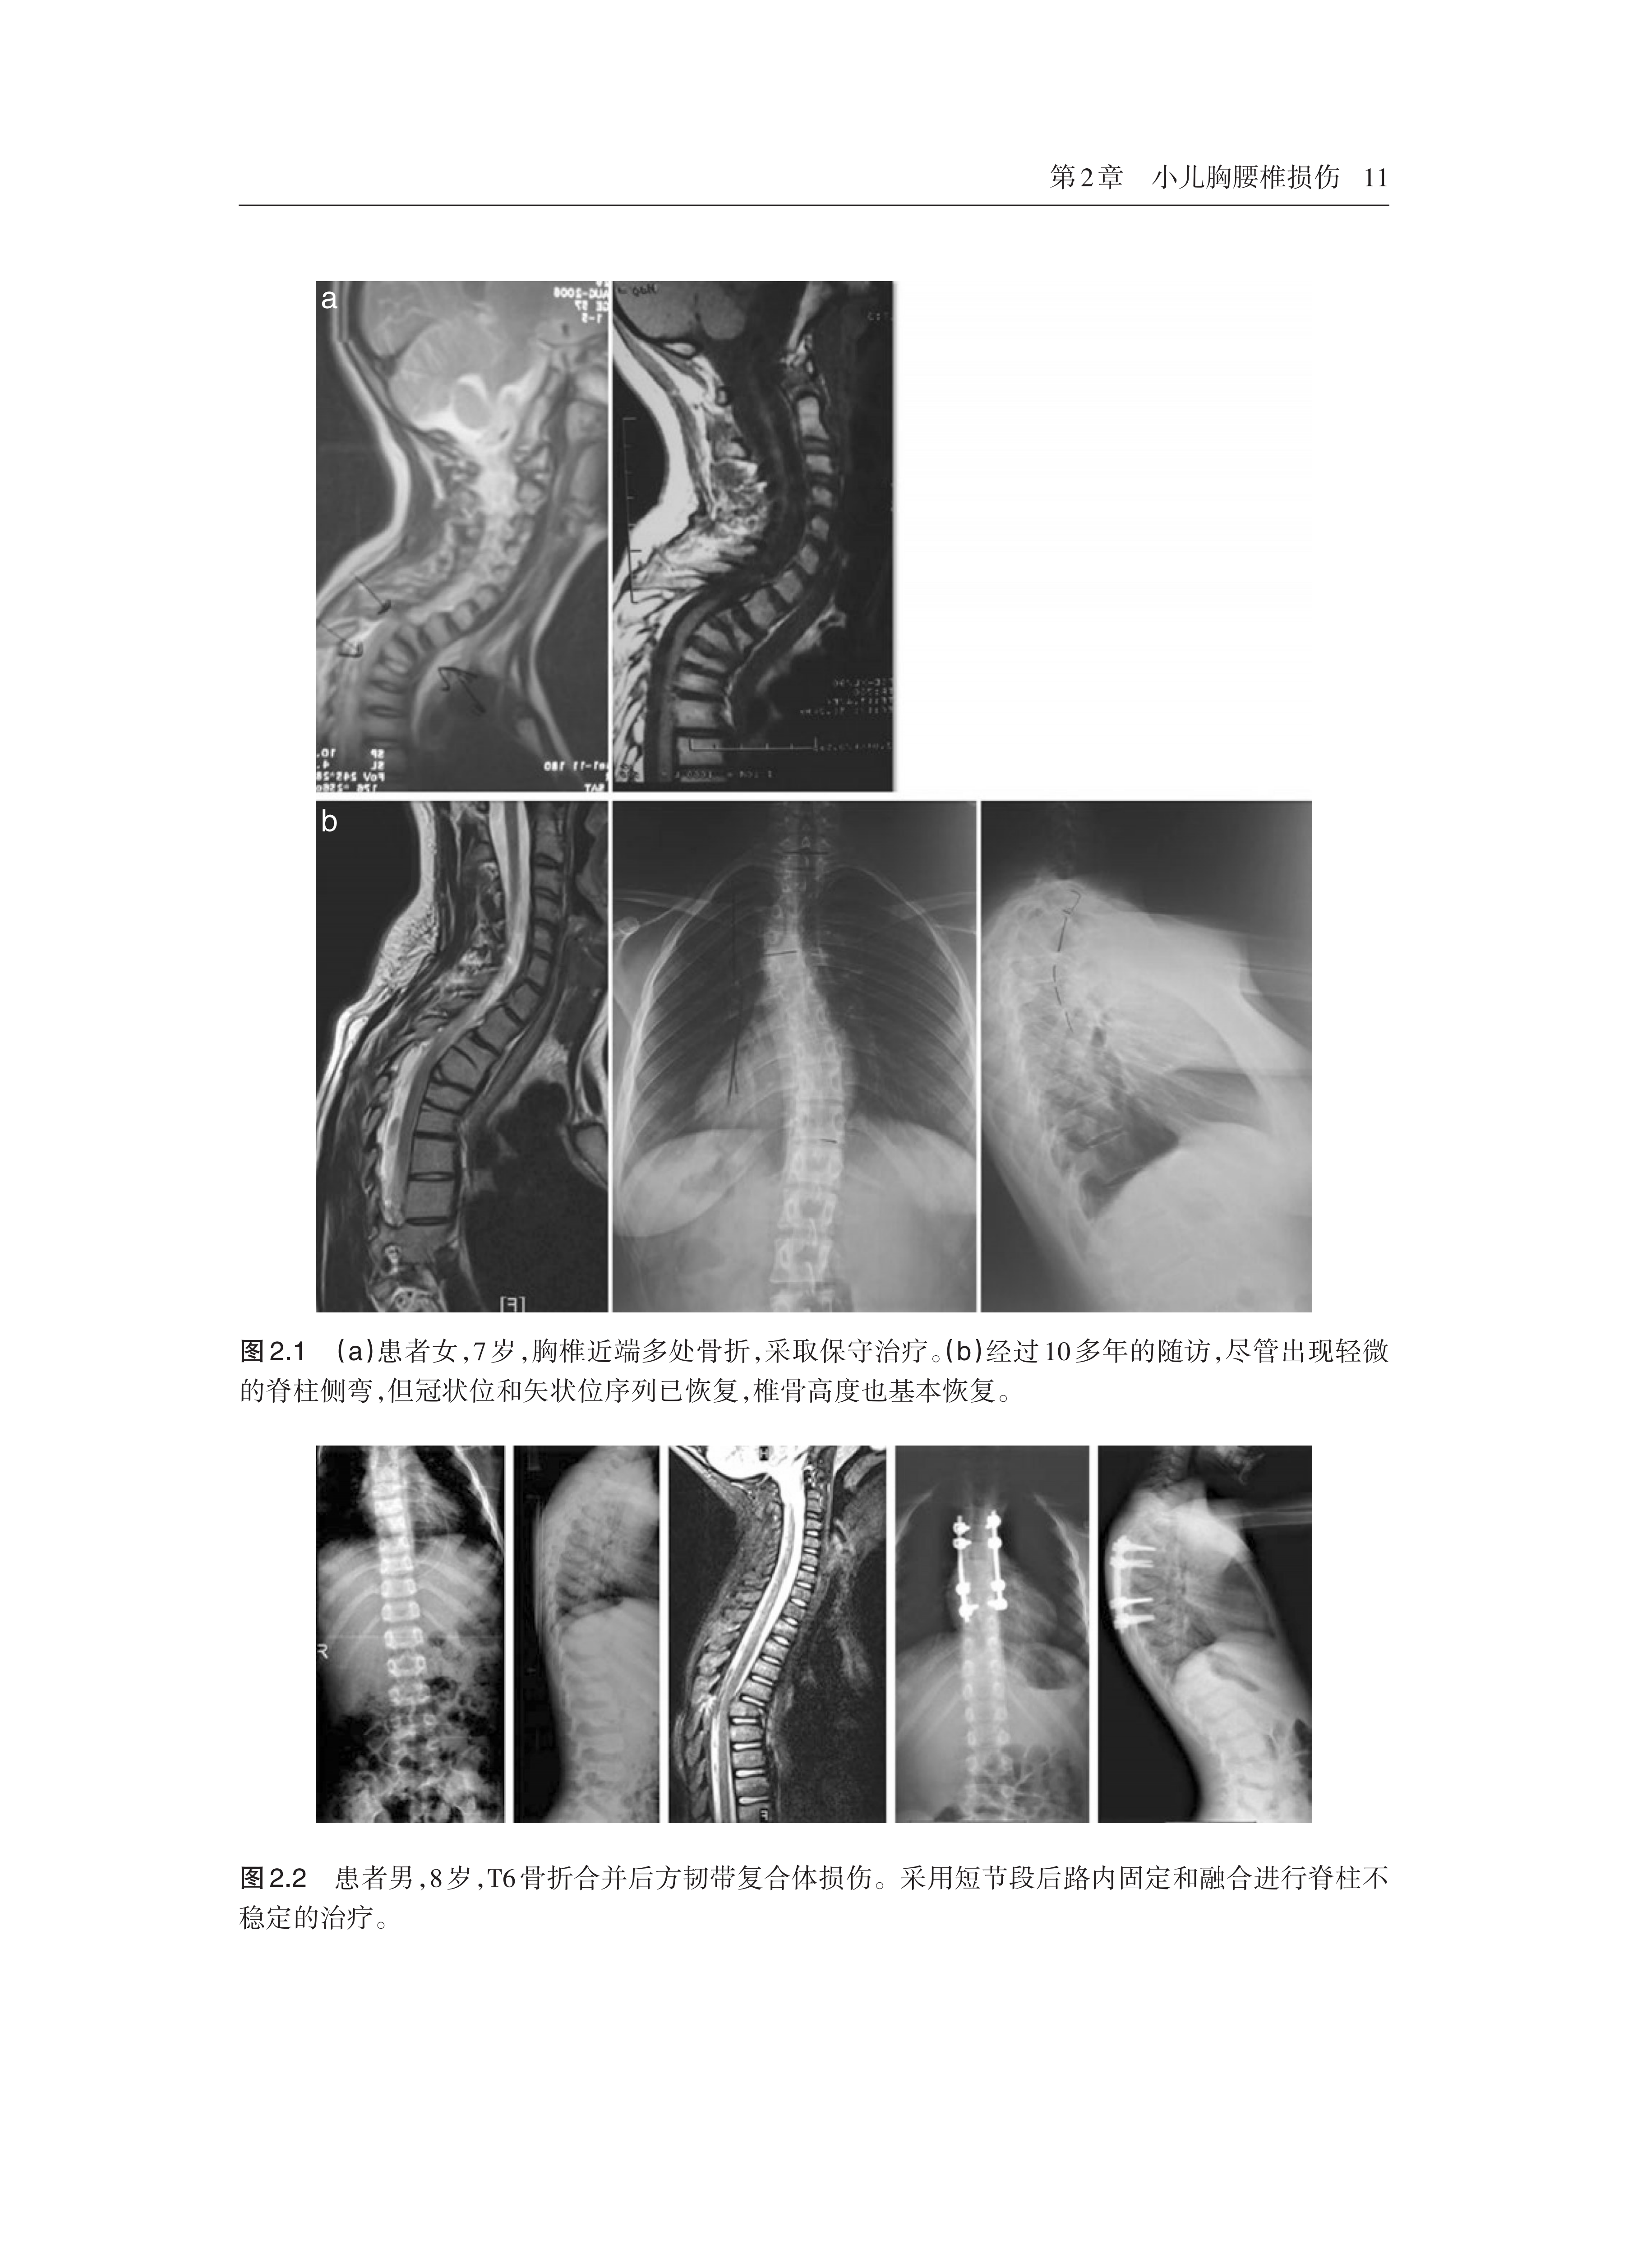

图文并茂,配有大量的临床图片,读者可扫描书中二维码观看高清彩图和原版教学视频,方便读者将知识应用于临床实践。